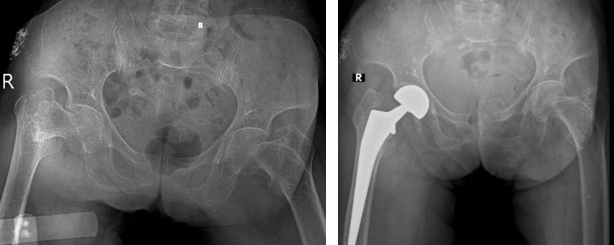

• Phương pháp thay khớp háng: Thay khớp háng nhân tạo này được chỉ định cho những trường hợp gãy liên mấu chuyển không vững đồng thời phát hiện tình trạng loãng xương, không thể tiến hành điều trị bằng bảo tồn hay kết hợp xương.

Thay khớp háng